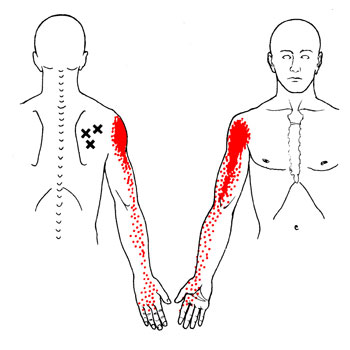

Oui! La douleur peut être causée par le syndrome myofascial et les points trigger myofasciaux. Ce n’est pas une maladie imaginaire, le syndrome myofascial et les points myofasciaux existent vraiment et malheureusement ils sont peu connus de notre système de santé traditionnel. Ils peuvent vous rendre la vie misérable. Eh, oui! Les points trigger ont passé l'art de mimer les symptômes de certaines maladies, de quoi laisser perplexe le meilleur des médecins.

Pour moi qui suis massothérapeute, ils font partie de mon quotidien. Je traite des gens à tous les jours avec des douleurs aux épaules, au cou, aux genoux, mal de dos, etc. Il m’arrive souvent de voir des gens qui ont très mal et qui ne savent plus quoi faire pour soulager leurs maux. Malheureusement, la massothérapie est souvent leur dernier recours. Ils ont souvent tout essayé, mais leurs douleurs persistent. Dans bien des cas il s’agit d’un durcissement du fascia et de points trigger. De deux à trois traitements suffirent dans bien des cas pour qu’ils retrouvent leurs qualités de vie qu’ils avaient auparavant.

Ils me disent tous la même chose! J’aurais dû venir te voir avant, car j’ai dépensé une fortune en médicament et en traitement! Alors la prochaine fois que vous avez une douleur quelconque, il se pourrait bien que la cause soit le syndrome myofascial et les points trigger myofasciaux!